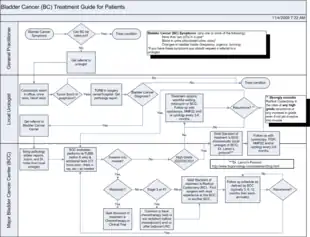

The treatment of bladder cancer depends on how deeply the tumor invades into the bladder wall.

Treatment strategies for bladder cancer include:[97][98]

- Non-muscle invasive: transurethral resection of bladder tumor (TURBT) with or without intravesical chemotherapy or immunotherapy

- Muscle invasive

- Stage II/Stage IIIA: radical cystectomy plus neoadjuvant chemotherapy (multimodal therapy, preferred) or transurethral resection with chemoradiation (trimodal therapy, highly selected people) or partial cystectomy plus neoadjuvant chemotherapy (in highly selected people)

- Stage IIIB/IVA: cisplatin-based chemotherapy followed by radical cystectomy or chemoradiation or observation depending on treatment response

- Stage IVB (locally advanced; unresectable tumors): palliative radiotherapy

- Metastatic disease: cisplatin-based chemotherapy

- Metastatic disease but unfit for cisplatin-based chemotherapy: carboplatin-based chemotherapy

- Metastatic disease with contraindication for chemotherapy: checkpoint inhibitors if programmed death ligand 1 (PD L1) positive

- Squamous cell carcinoma or adenocarcinoma of bladder: radical cystectomy